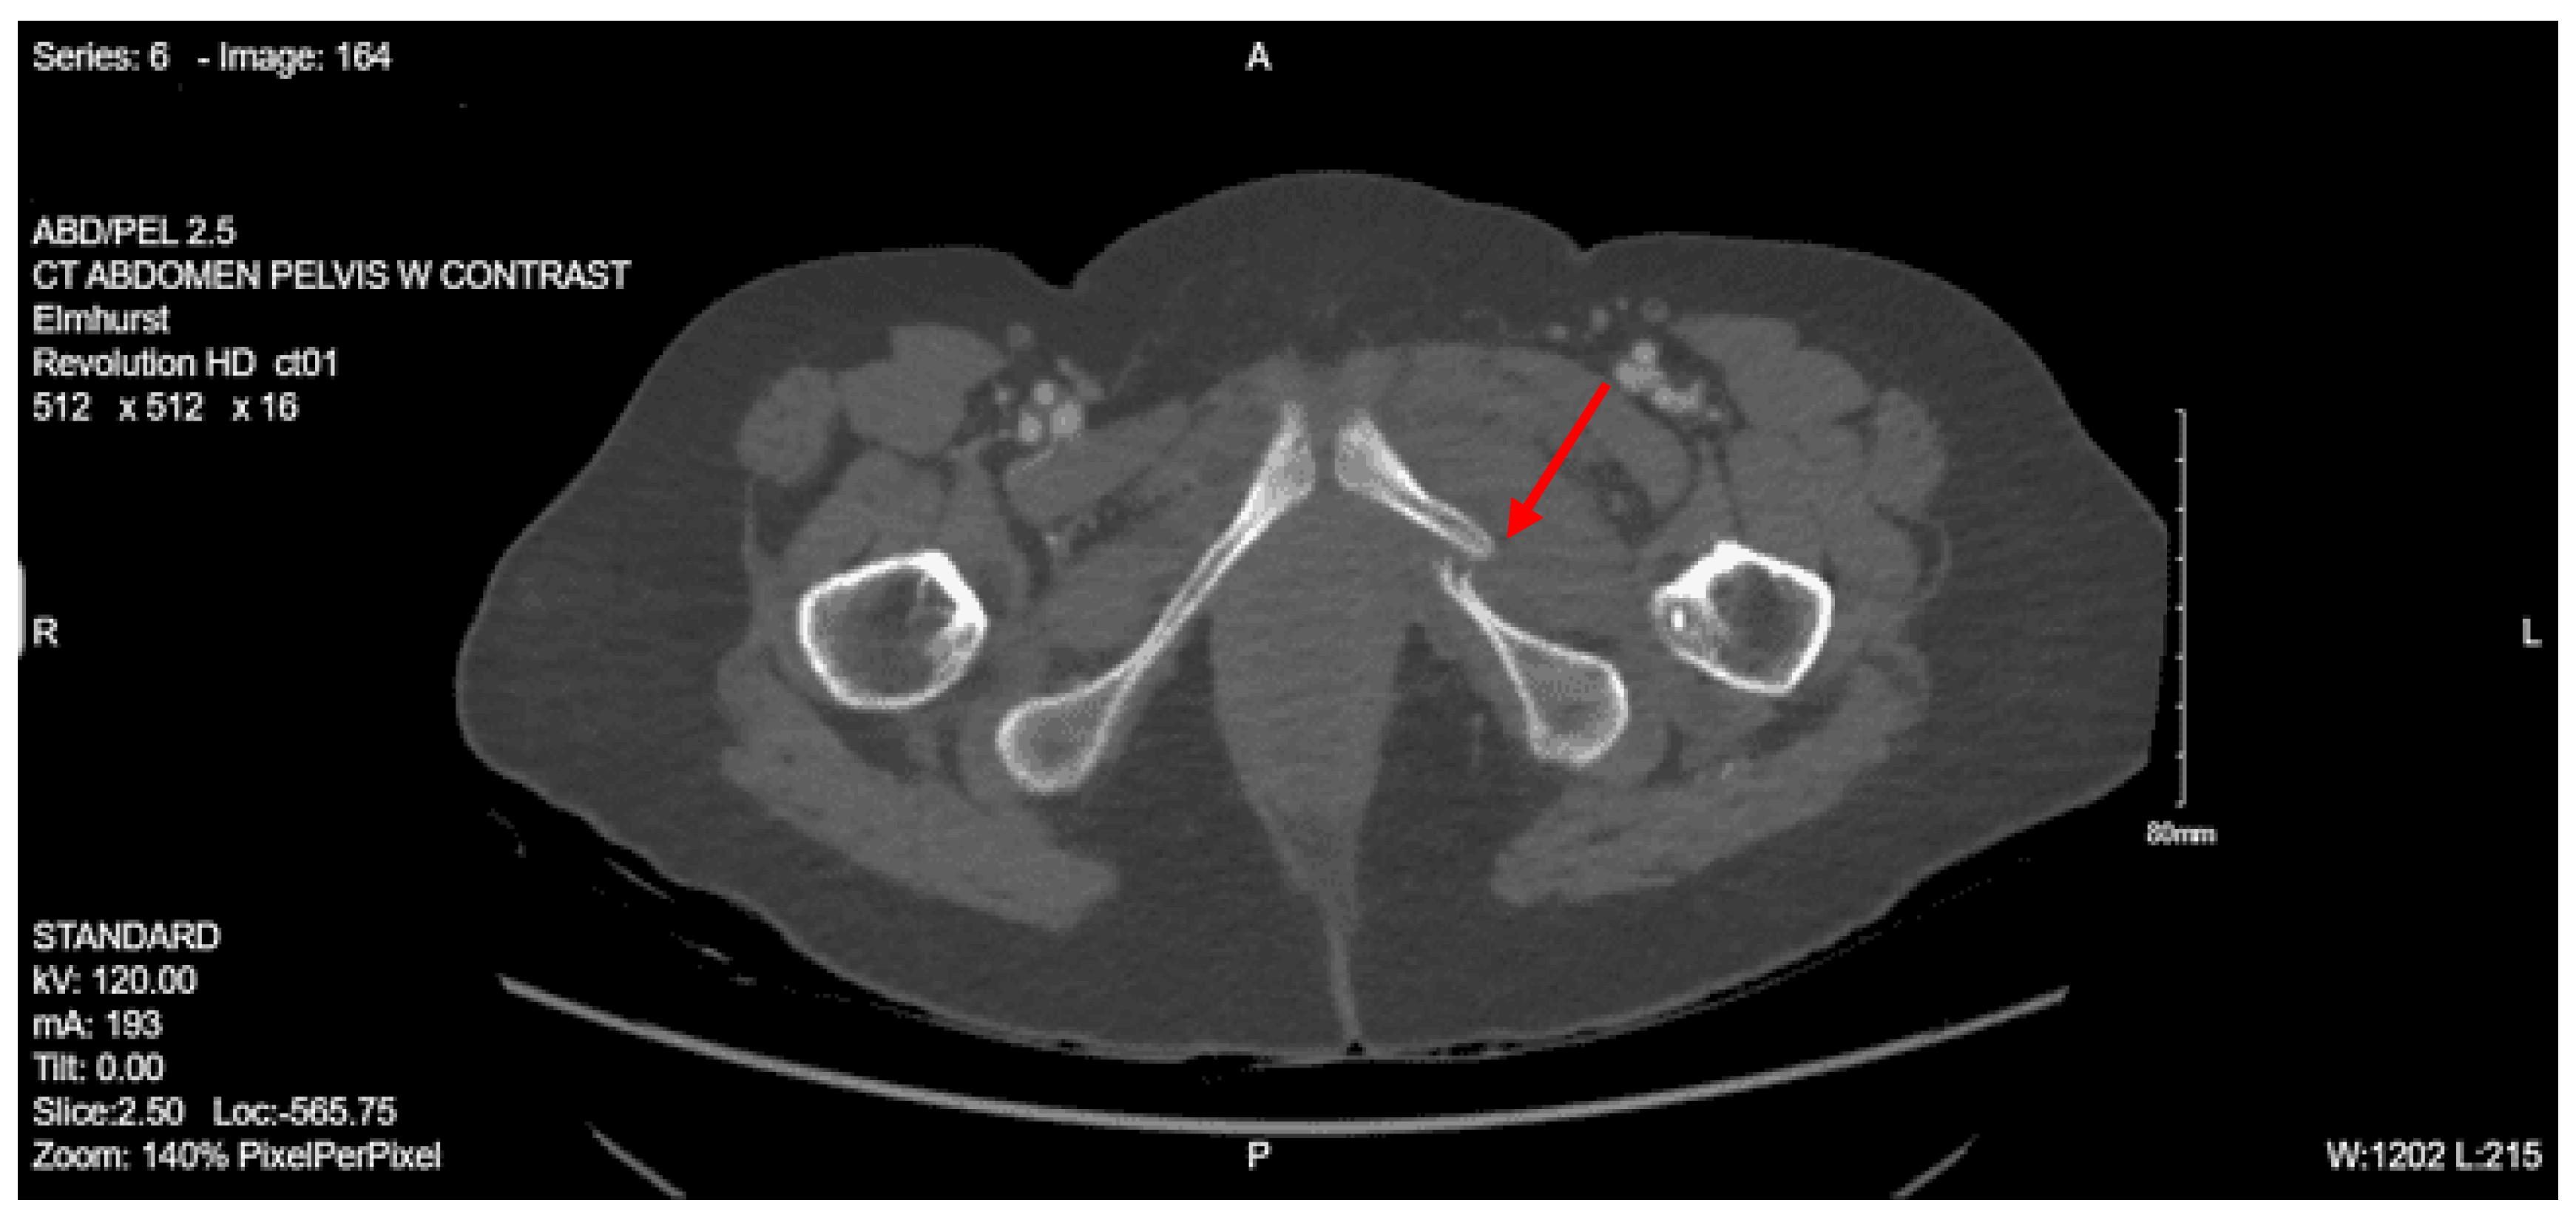

Imaging as shown in Figure 27, Figure 28 and Figure 29:

CT abdomen pelvis with contrast: There is retroperitoneal fluid surrounding the upper abdominal aorta without contrast blush. Linear flap within the upper abdominal aorta at the level of the celiac and SMA origins, concerning for traumatic injury. Lower thoracic findings include multiple posterolateral right rib fractures. Grade II hepatic injury. Periportal edema. Acute right L1 through L5 transverse process fractures. Acute right sacral ala fracture. Nondisplaced acute right inferior pubic ramus fracture. Nondisplaced acute fracture involving the lateral aspect of the right acetabulum.